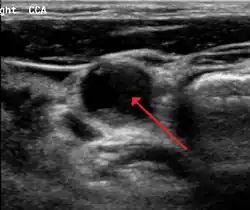

Le diagnostic est fait par échographie Doppler. Cet examen, non invasif, permet de visualiser les artères carotides, la présence ou non d'athérome et de quantifier le degré d'obstruction. Cet examen est demandé soit devant la présence d'un souffle carotidien à l'auscultation des vaisseaux du cou, soit à titre systématique chez un patient ayant déjà fait un accident vasculaire cérébral ou ayant un athérome sur une autre artère (artériopathie oblitérante des membres inférieurs ou maladie des artères coronaires.